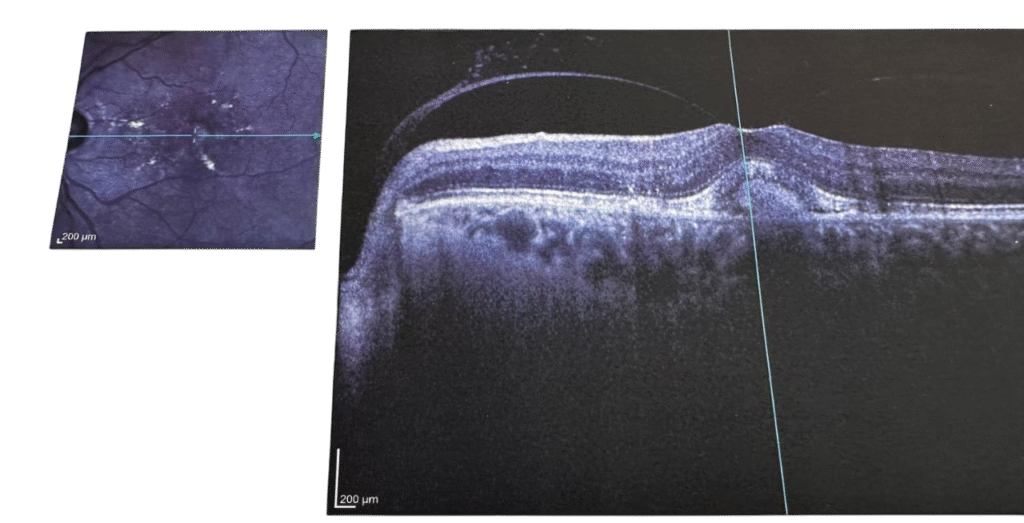

Resim 2: Sarı nokta hastalığı tedavi sonrası

YAŞ TİP SARI NOKTA HASTALIĞI

Görme noktasının altında olmaması gereken yeni bir zar gelişir. Damarsal yapısı çok yüksek olan bu zar; foveanın (sarı nokta) altına sıvı ve kan sızıntısına sebep olur . Retinanın içinde sıvı birikmesi merkezi görmeyi bozar. Bu yapıyı söndürmek için göz içinde damar oluşumunu sağlayan faktörleri yok eden maddeleri içeren enjeksiyonlar yapılmalıdır. Tedavi protokolü standarttır. Başlangıçta yükleme dozu olarak 1 er ay arayla 3 defa enjeksiyon yapılır, daha sonra hastalığın gösterdiği gelişme göre hastalar ayda bir ya da daha geniş aralıklarla kontrol edilir. Aktivasyon varsa enjeksiyonlara devam edilir. Göz sakin bulunursa o seans atlanır. Enjeksiyonların ucu açıktır ve kaç enjeksiyon gerekiyorsa mutlaka yapması gerekir.

Eğer hasta takipten çıkarsa bu sönmümlenmiş zar tekrar aktive olup, sıvı üretimine sebep olabilir ve hastalıkta başa dönülür. Bir başka deyişle; çim ekilmiş bir bahçede yabani otları ilaçla yok edebilirsiniz, ancak daha sonra yenileri geliştiğinde tekrar ilaçlanması gerekir. Yaş tipte de, kuru tipte olduğu gibi; sağlıklı beslenme şeklimizi devam ettirmemiz, takviye vitaminleri, mineral ve omega 3 içeren takviyeleri almamız ve güneşten korunmız şarttır .